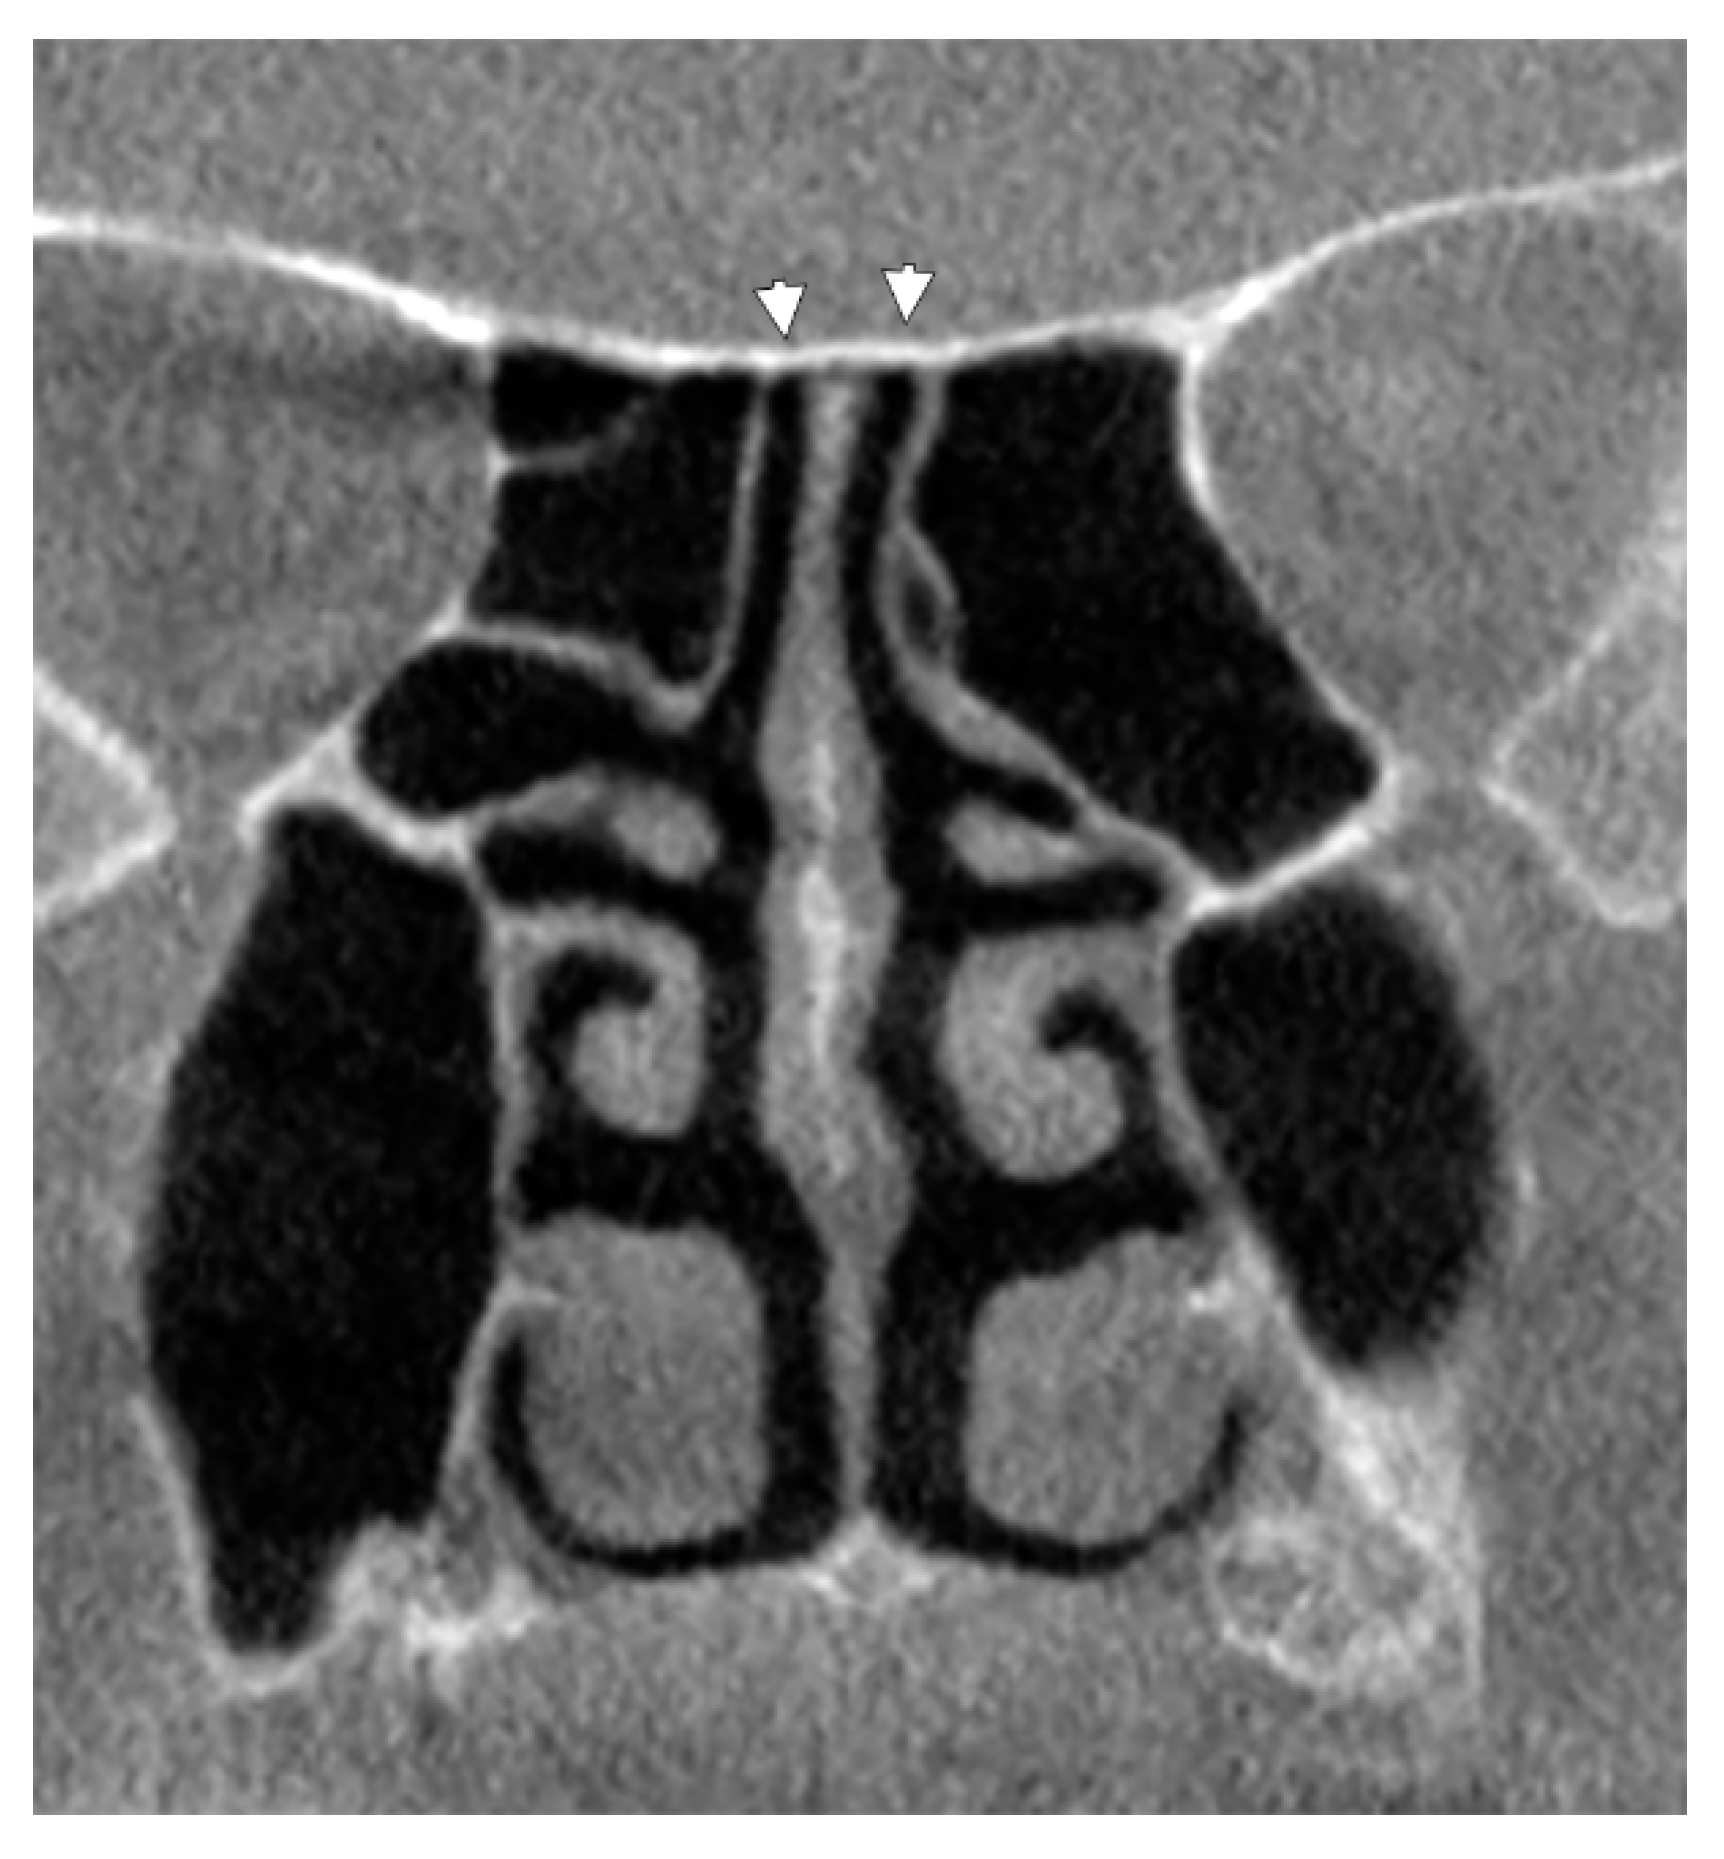

3.1. Ethmoidal Origin of Nasal Roof Pneumatizations